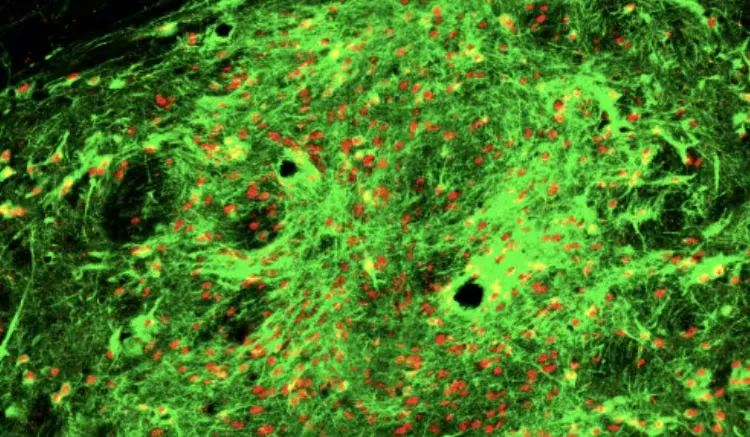

通过SISBAR技术鉴定的表面标记分子可以高效富集多巴胺能神经细胞。图片显示的是小鼠脑内移植的人中脑多巴胺能神经元。红色标记的是人的细胞核,绿色标记的是多巴胺能神经元的标志蛋白TH。

图注:(A)用于跨时间点克隆谱系追踪的SISBAR实验设计示意图。(B)跨越四个分化阶段多层级谱系树,展示了不同分化时间段不同细胞类型之间显著的遗传谱系关系。(C-D)两种不同的汇聚型谱系分化路径示意图。(E)特异性表达在中脑多巴胺能神经元早期前体细胞中的基因。(F)未分选的神经前体细胞和APCDD1+神经前体细胞衍生的移植物典型图和移植物中TH+神经元的比例,hN,人源细胞核。比例尺,大图中为100μm,小图中为20μm。

研究团队进一步展示了基于SISBAR技术的跨分化阶段谱系关系和相关分子调控机制的解析在神经系统疾病细胞治疗中的应用。利用SISBAR技术,研究团队发现中脑多巴胺能神经前体细胞具有至少三种命运分化潜能,包括中脑多巴胺能神经元、中脑谷氨酸能神经元、血管软脑膜样细胞(VLMCs)。研究团队还鉴定了早期中脑多巴胺能神经前体细胞的特异性表面分子标记物APCDD1(图E)。将表达APCDD1的神经前体细胞进行流式分选并移植到帕金森病模型小鼠的纹状体后,移植物中目的细胞-中脑多巴胺能神经元的比例得到了显著提高(图F)。并且,与通过SISBAR技术发现的中脑多巴胺能神经前体细胞多分化潜能的结果一致,研究团队在APCDD1分选的移植物中检测到了中脑谷氨酸能神经元和一种血管软脑膜样细胞的存在,这一结果展示了SISBAR技术在改进细胞治疗策略和预测移植细胞体内分化命运中的应用。